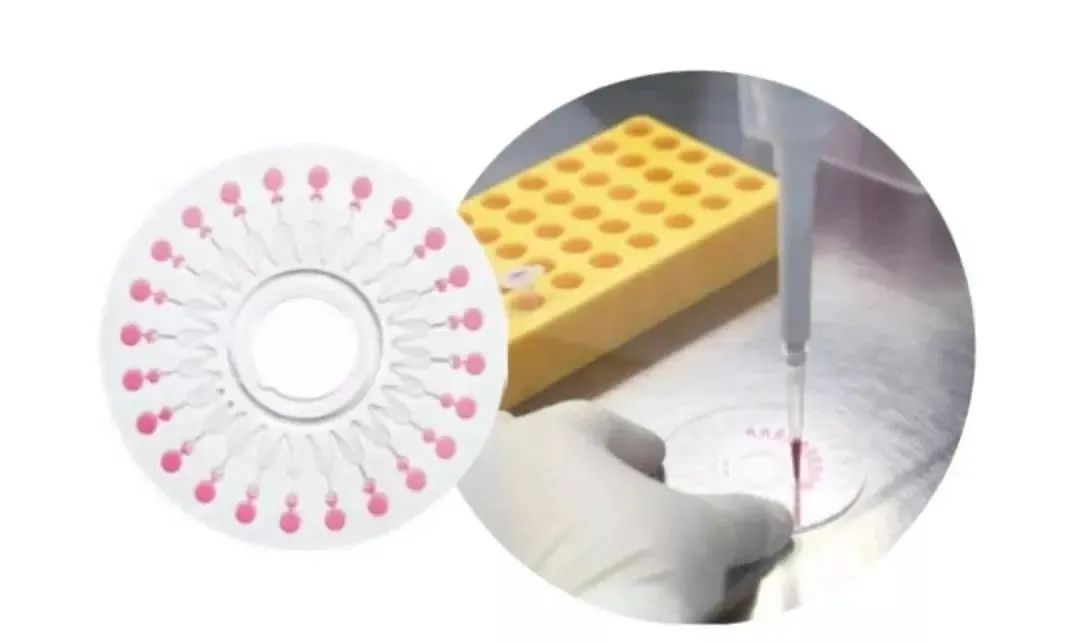

六项呼吸道病毒核酸检测试剂盒

1.5小时内出检测结果

疫情爆发时,如何能在第一时间

确定患者是否感染新型冠状病毒

那绝对离不开新型冠状的检测试剂盒

同样是受命于危难之际

博奥生物联合清华大学

和四川大学华西医院共同设计开发了

6项呼吸道病毒核酸检测试剂盒

图片来源:清华大学

这是全球首个

能在1.5小时内一次性检测

包括新型冠状病毒在内的

6项呼吸道病毒核酸检测芯片试剂盒

检测时只需采集患者的

口、咽拭子等分泌物样本

过程简单,出结果也快

这样就能快速对患者鉴别诊断

及时针对性治疗

大大减轻医院的负担

图片来源:博奥生物

对于现在疫情爆发的许多国家

他们也急需中国提供的检测试剂盒

帮助更快的筛查和确诊